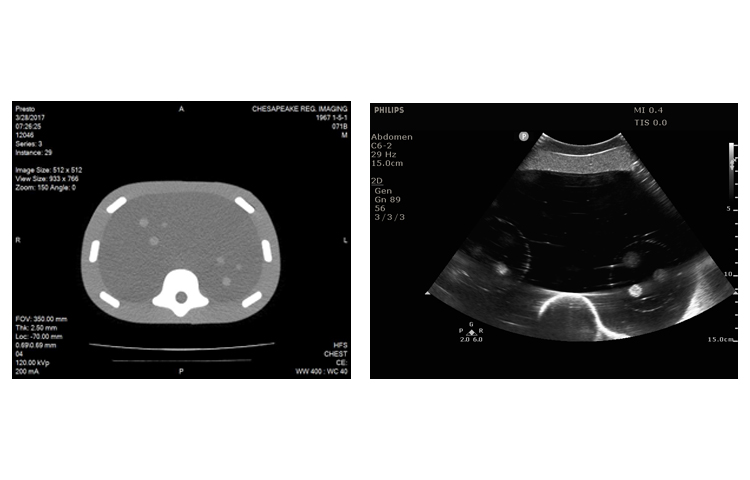

CIRS 071B圖像引導腹部穿刺模體是一種簡化的腹部模型,適用于訓練和演示圖像引導的穿刺活檢導航工具或程序,需要持續的視覺參考針頭放置。因為它是由Zerdine的自我修復配方構成,所以體模允許多次活組織檢查插入,最小的針跟蹤。

CIRS 071B圖像引導腹部穿刺模體包含12個病灶,直徑5-12mm,以三個一組的方式放置在體模內的一致位置。它還包括模擬脊柱和肋骨,以及脊柱內的“H”標記,以幫助確定CT圖像中的頭側。

在超聲,CT和MRI下可見病變和脊柱。固體聚合物凝膠背景是消聲的,穿刺時不會泄漏。